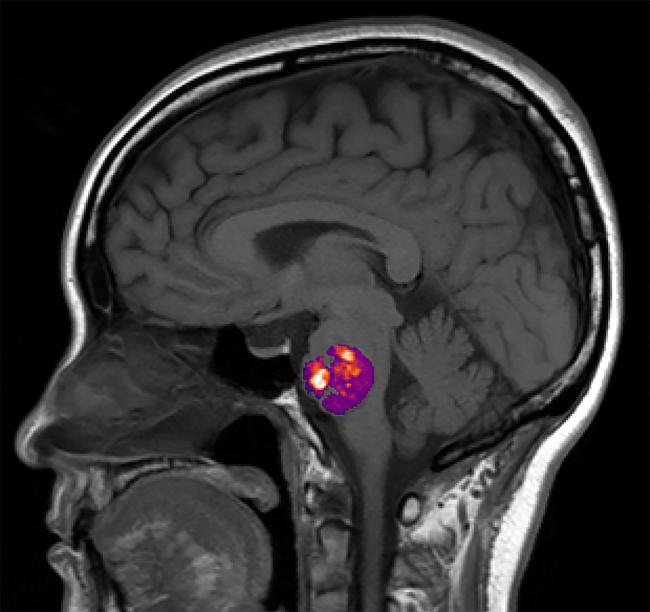

In a nationwide study, NIH funded researchers found that the presence of abnormal bundles of brittle blood vessels in the brain or spinal cord, called cavernous angiomas (CA), are linked to the composition of a person’s gut bacteria. Also known as cerebral cavernous malformations, these lesions which contain slow moving or stagnant blood, can often cause hemorrhagic strokes, seizures, or headaches. Current treatment involves surgical removal of lesions when it is safe to do so. Previous studies in mice and a small number of patients suggested a link between CA and gut bacteria. This study is the first to examine the role the gut microbiome may play in a larger population of CA patients.

Led by scientists at the University of Chicago, the researchers used advanced genomic analysis techniques to compare stool samples from 122 people who had at least one CA as seen on brain scans, with those from age- and sex-matched, control non-CA participants, including samples collected through the American Gut Project. Initially, they found that on average the CA patients had more gram-negative bacteria whereas the controls had more gram-positive bacteria, and that the relative abundance of three gut bacterial species distinguished CA patients from controls regardless of a person’s sex, geographic location, or genetic predisposition to the disease. Moreover, gut bacteria from the CA patients appeared to produce more lipopolysaccharide molecules which have been shown to drive CA formation in mice. According to the authors, these results provided the first demonstration in humans of a “permissive microbiome” associated with the formation of neurovascular lesions in the brain.